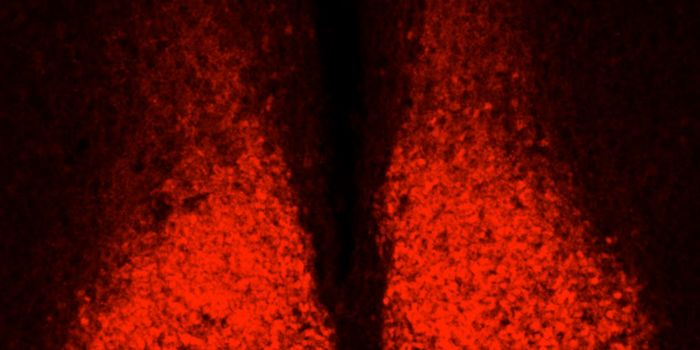

NOV 03, 2021Genetics & GenomicsIn Parkinson's disease, neurons that produce the neurotransmitter dopamine in a part of the brain called the substantial ...